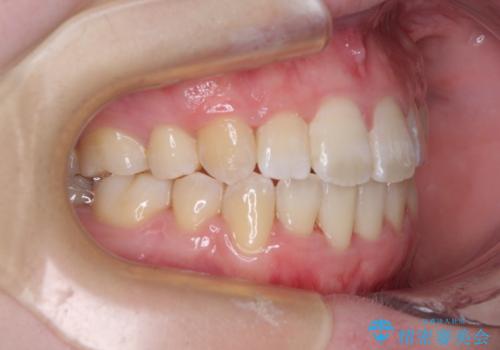

上下非接触で突出した前歯 ワイヤー装置による抜歯矯正

- 上下前歯の隙間と口元の出っ張った感じを気にして来院された患者様です。

上下の隙間は舌突出癖によるもので、またその癖により前歯が前方に出ている状態でした。

口元の出っ張りを改善するため、上下左右第一小臼歯4本を抜去し、ワイヤー装置にて矯正治療を行うこととしました。